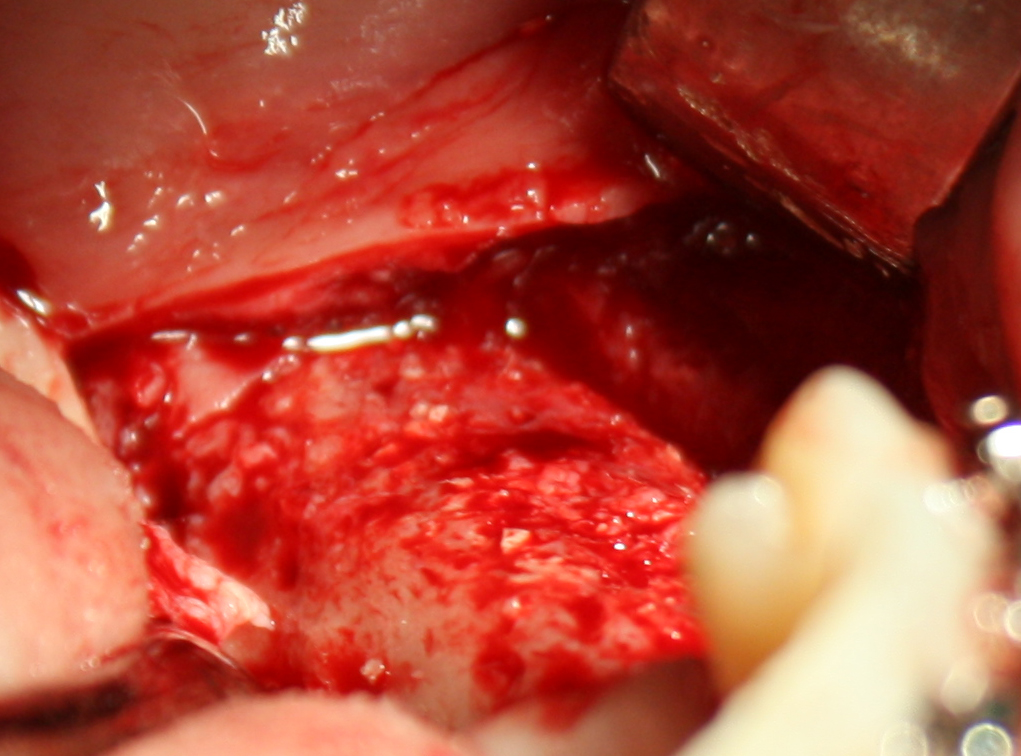

В этом случае остеопластика делается отдельной процедурой. Ее принципы точно те же, но уже без импланта. Например:

Имплантировать в таких условиях — заведомо обрекать себя на хреновый, с точки зрения эстетики и функциональности, результат. Поэтому первым этапом проводим остеопластику. Объем небольшой, использовать в таких объемах костный блок не очень рационально. Воспользуемся аутокостной стружкой и мембраной.

Сначала фиксируется BioGide. Это легко:

Затем укладывается и конфигурируется аутокостная стружка: